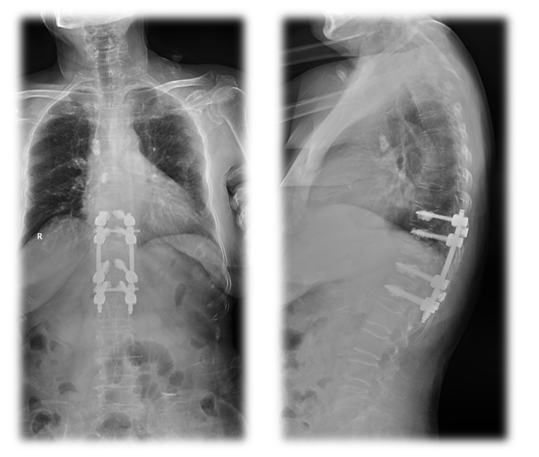

手术治疗:T10-T12棘突椎板切除;T11 截骨后凸矫形;T9-L1椎弓根固定,均为骨水泥螺钉,安放横联两根;T10/11及各椎板后方大量植异体骨及自体骨。

术中透视

术后X线

术前后侧位

术后CT